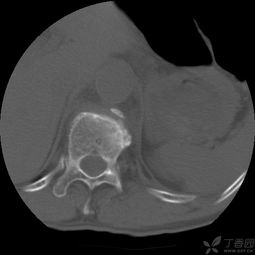

由于X線檢查技術(shù)的進(jìn)步,特別是CT、MRI的應(yīng)用,使人們確信脊柱骨折中脊髓神經(jīng)所受的打擊或壓迫大多來(lái)自硬脊膜前方,施行前路減壓術(shù)有了肯定的理由。但是前路手術(shù)因?yàn)樯婕靶?、腹腔臟器及重要血管等結(jié)構(gòu)較多,手術(shù)難度較大,術(shù)后并發(fā)癥多,不僅對(duì)病人的全身、局部情況要求較高,而且也要求醫(yī)生掌握扎實(shí)的基礎(chǔ)理論和豐富的臨床經(jīng)驗(yàn),具備熟練的手術(shù)技巧。

例如爆裂型骨折存在下述3種情況時(shí),就需行前路減壓術(shù):1.合并嚴(yán)重神經(jīng)系統(tǒng)癥狀,或伴有進(jìn)行性神經(jīng)功能惡化的;2.就診較晚已超過(guò)2周以上者;3.脊柱CT掃描斷層顯示已有較大的骨折片突入椎管內(nèi),使椎管變窄超過(guò)30%以上,預(yù)示后縱韌帶已有明顯損傷,使用后路手術(shù)方法,已無(wú)法使骨折片復(fù)位;4.無(wú)神經(jīng)壓迫癥狀,椎管壓迫超過(guò)50%,需要對(duì)畸形進(jìn)行矯正者。 胸腰椎骨折在臨床上較多見(jiàn),如果護(hù)理不當(dāng), 會(huì)給患者造成終生殘疾。